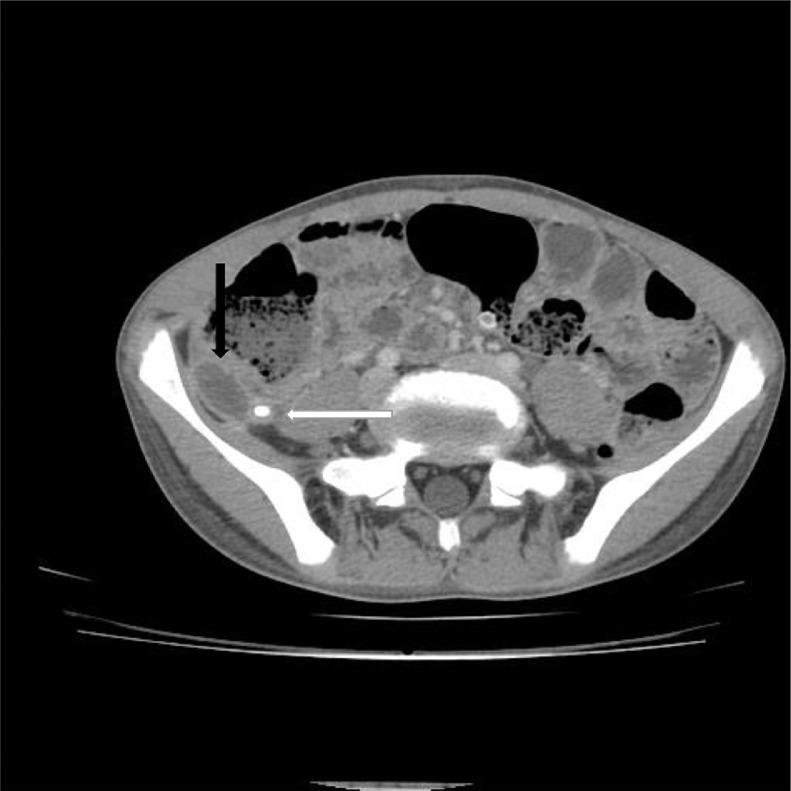

Retrocecal appendicitis usually presents with atypical signs and symptoms which may lead to delayed diagnosis, perforation and serious complications. Development of a large lung abscess secondary to perforation of retrocecal appendicitis in an adolescent patient is an extremely rare entity and to the best of our knowledge has not been described in literature. We present a 15-year-old boy with complaint of chest pain, cough, fever, vague abdominal pain and raised inflammatory markers who underwent CT examination. On CT, a collection with focal calcification was noted in the right iliac fossa that extended along the right retroperitoneum through the retrocrural space in the right lung base communicating with a cavitary pulmonary lesion with air-fluid level. A diagnosis of perforated retrocecal appendicitis with retroperitoneal and right lung abscesses was made. The patient underwent appendectomy and the entire retroperitoneal and lung abscesses were drained. A lung abscess as a complication of perforated retrocecal appendicitis should be in consideration in septic patients with thoracoabdominal infectious manifestations.